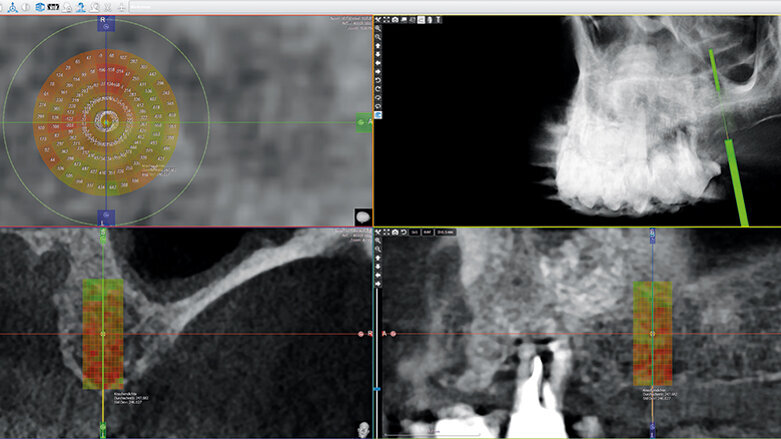

Vzhledem k tomu, že úbytek alveolární kosti způsobený přirozenou atrofií nebo destruktivními iatrogenními procesy v době extrakce zubu vyžaduje okamžité (zachování alveolárního hřebene) nebo pozdější (řízená regenerace kosti) procedury augmentace kosti, zjistili Di Lallo a kol. (2014) a Troedhan a kol. (2014) v randomizovaných klinických studiích, že je podstatný rozdíl v primární stabilitě implantátu, pokud jde o augmentovanou alveolární kost a nativní alveolární kost. Nedávno provedl Troedhan a kol. (2019) další randomizovanou klinickou studii, která zkoumala, zda by bylo možné dokázat významnou souvislost mezi prechirurgickou CBCT kostní denzitometrií provedenou pomocí X-MIND TRIUM CBCT (ACTEON) a primární stabilitou implantátu v augmentovaných oblastech maxilárního sinu.

Obrázek 1 zachycuje "split-mouth" případ s oboustranným zákrokem přístrojem INTRALIFT: po oddělení malého krestálního laloku ve tvaru „knížečky“ o rozměru cca 7 × 7 mm bylo dno sinu bezpečně otevřeno pomocí ultrazvukových hrotů Piezotome (obr. 2, 3), membrána sinu oddělená vlivem hydrodynamického kavitačního účinku hrotu Piezotome TKW5 pak byla vtlačena do přístupového kanálu (obr. 4, 5), subantrální konstrukce byla vyplněna 2 cm náhodně přiřazeného biomateriálu a následně byla rána sešita.